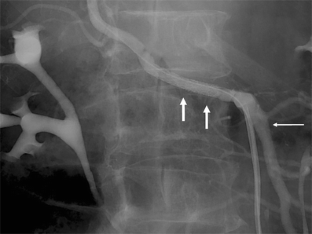

Fig. 1